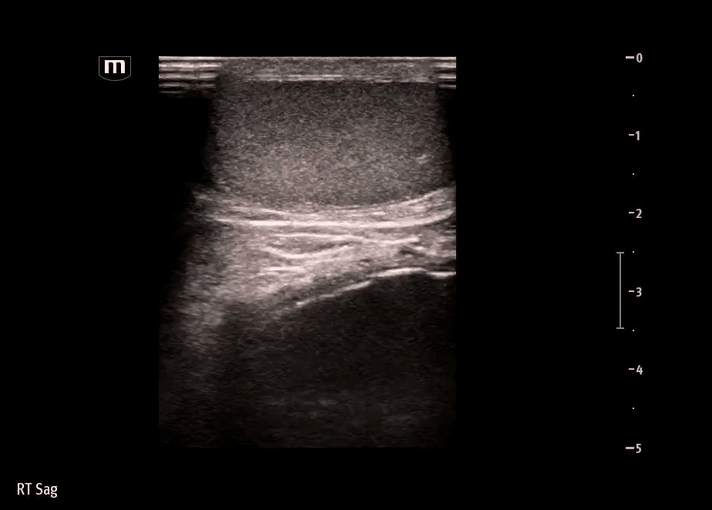

Ultrasound:

Ultrasound was performed on the R scrotum

Findings on our bedside ultrasound:

• The structure is anechoic - fluid-filled, appears to be simple fluid

• The structure has no peristalsis, and there is a lack of typical bowel wall findings - probably not bowel or inguinal hernia

• The structure does not seem to be within the tunica vaginalis - not a hydrocele, where the simple fluid collection would be seen surrounding the testicle itself

In comparison, our image didn’t show typical bowel wall appearance but the swelling/mass was located within the scrotum, so what did the hernia contain?